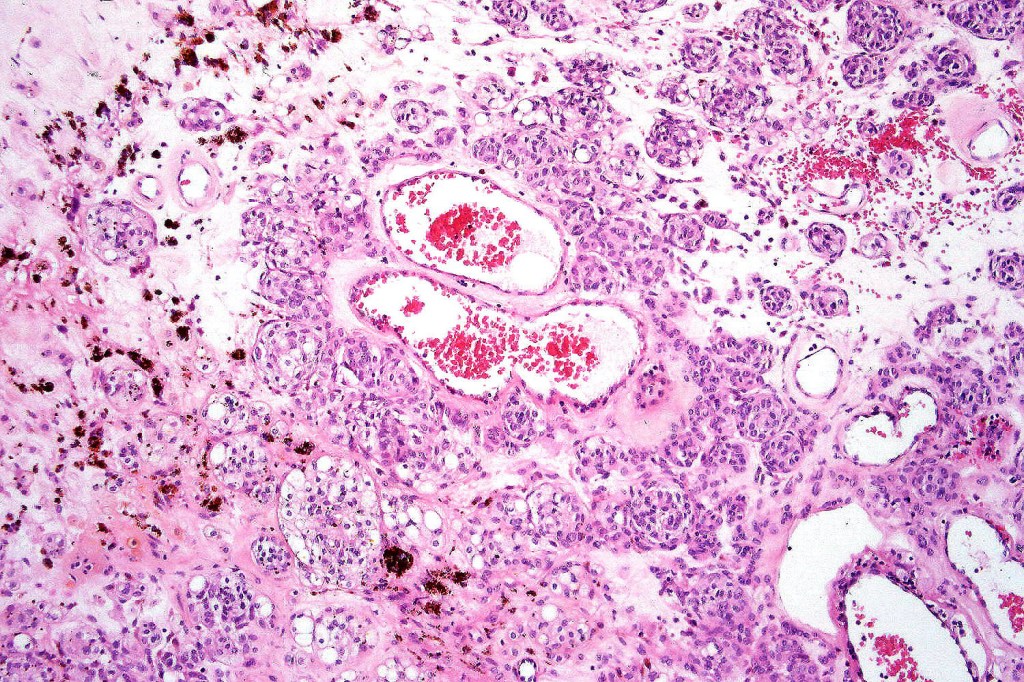

Cellular blue nevus

This uncommon most often devlops on the buttocks, sacrococcygeal region & distal extremities although it may be seen at just about any site. It shows a predilection for females and is diagnosed most often in the 2nd-4th decade. It presents as a blue-black/ or black nodule measuring 1-2 cm in dianeter. Similar to common blue nevus, the cellular variant can be encountered in a wide range of non-cutaneous locations.

Histological features

•Most characteristic is the dumbbell silhouette although a plague morphology may also be encountered

•Combined nevus variant

•Admixture of spindle cells, pigmented bipolar or dendritic cells & melanophages

•Cytoplasm is pale and nuclei are small with inconspicuous nucleoli

•An alveolar pattern is characteristic particularly with clear cell nodules

•Mitoses are typically very sparse or absent

•No atypical mitoses

•No Necrosis or lymphovascular invasion

•Multinucleate giant cells sometimes present

•Stromal fibrosis, myxoid change, vascular hyalinization with cyst formation are often seen

•Some tumors are composed spindle cells in a fascicular or neuronevoid pattern

•Perineural involvement may be seen

•Balloon cell change

•Desmoplastic variant

•Hypopigmented variant